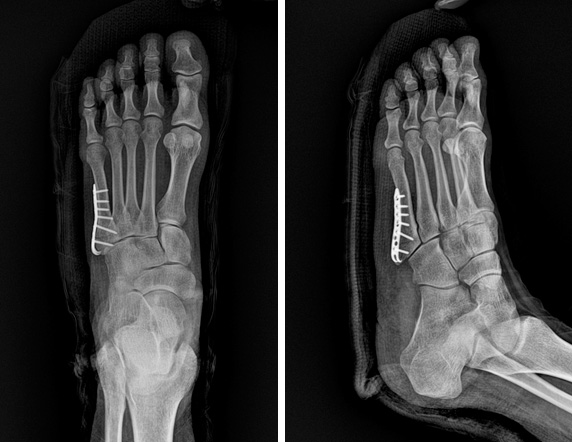

또한, 복합 골절이나 압박 골절과 같이 더 복잡한 경우에는 수술이 필요할 수 있으며, 뼈가 조각나거나 비스듬하게 부러진 경우에는 금속판을 추가적으로 사용할 수 있습니다.

- 압박골절로 조각이 많이 발생한 경우: 많은 골조각이 발생한 경우, 수술을 통해 정확한 정렬과 고정이 필요합니다.

- 수술 치료: 뼈가 심각하게 파열되거나 개방성골절인 경우 수술이 필요합니다. 이 경우 수술비용은 약 60만원에서 150만 원까지 다를 수 있으며, 이 비용에는 입원비, 식비, 약값 등이 포함될 수 있습니다.